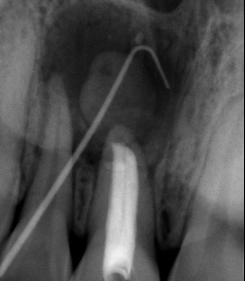

3. Radiografía periapical de una luxación extrusiva en el órgano dental 11

Trauma en niños y adolescentes: luxaciones

Figura